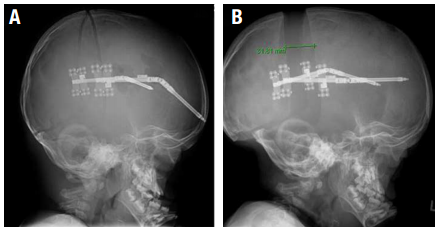

Stainless steel cranial expander springs are implanted after the closed suture is opened. The springs are then removed three months later. The level of spring force is selected based on the patient’s age, bone thickness, and head shape severity. Spring-assisted surgery is performed between the ages of three to six months. The springs require a second surgery for removal but not the use of the helmet.

In very rare cases, when most or all of the sutures are closed, cranial distraction can be used to create more space inside of the skull. After the bones are unlocked, distractors are implanted across the bone cut. At a rate of 1 mm (less than 1/16th of an inch) per day, the sides are separated by turning a small screw. After 30 days, 3 cm (almost 1 and 1/4 of an inch) of new bone is created. Three months later, the distractors are removed at a second surgery.